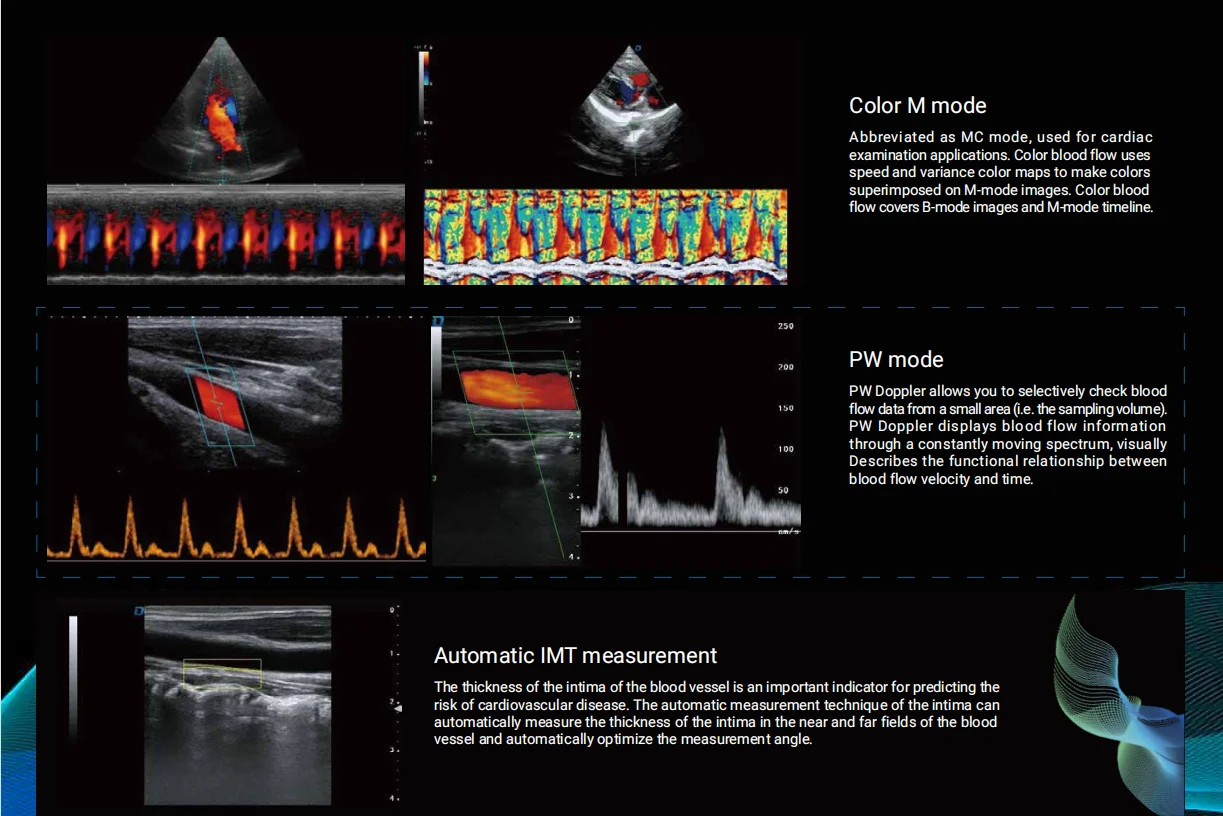

3.2. Digital beam intensifier

3.10. Spectrum Doppler imaging (including pulse Doppler, high pulse repetition rate, continuous wave Doppler)

3.11. Tissue Doppler imaging (including tissue velocity map, M mode, spectral imaging, etc.)

Clinical Images